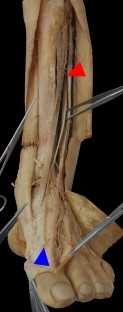

The accessory tendon of the EHL was found in 97.92% (47/48) of the legs that were dissected. In one male cadaver, an independent muscle belly was identified in each leg, whereas all the other accessory tendons originated from the main tendon of the EHL. In this study, the insertion of the accessory tendon were classified into four patterns. The most common insertion sites were the first metatarsophalangeal (MTP) joint capsule and proximal phalanx of the great toe. The length of the accessory tendons did not correlate with age or with sex when the two tendons with independent muscle belly were excluded.

The accessory tendon of the EHL appears to be a regular feature in Taiwanese people. Most accessory tendons of the EHL (85.7%) attached on the first MTP joint capsule may play a role in the prevention of capsular impingement during great toe extension.